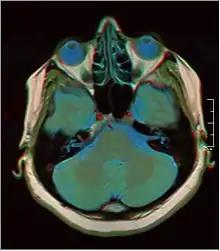

Brain regions on T1 MRI